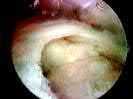

What is the most likely mechanism of failure for the patellar component shown: